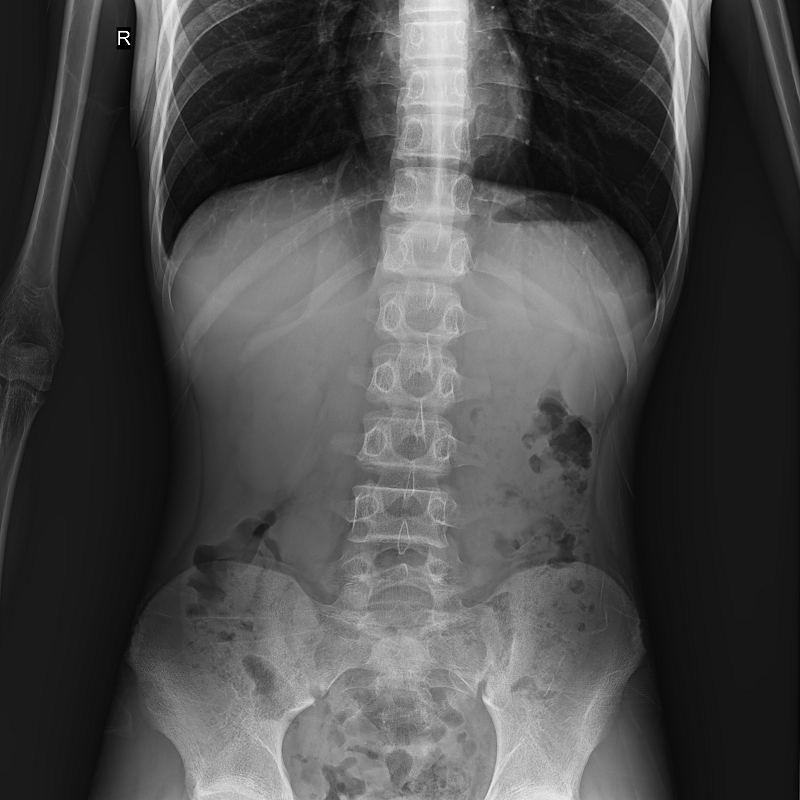

●呈現全下肢或全脊柱圖像

●在脊柱及下肢畸形矯正手術治療中,為術前方案制定和術后復查提供精準測量

●有效解決傳統X光片不能一次成像問題,為患者提供更加優質的醫療服務